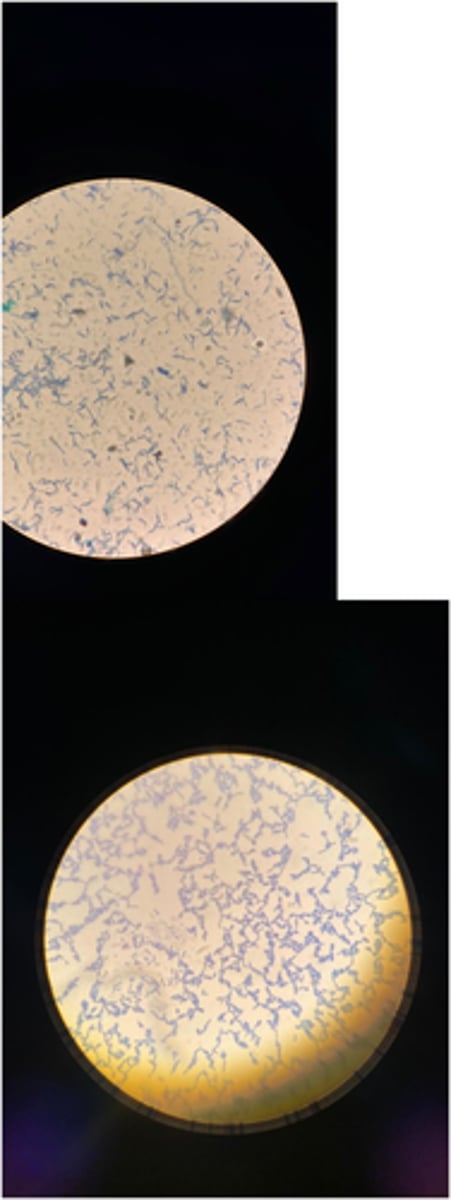

B. Anthracis

- Rods in chains - spore forming

- Gram Positive

- Simple agar - medusa head

- Simple broth - cotton like sediments

- Diseases: Cutaneous anthrax, GI anthrax, Pulmonary anthrax, meningitis

- Treatment: Antibiotics